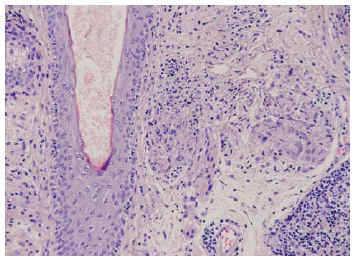

En el estudio histológico se observó una epidermis conservada y una dermis papilar y reticular alta ocupada por múltiples granulomas epitelioides con abundantes células gigantes, sin necrosis central, y rodeados de una corona linfocitaria compuesta por linfocitos maduros (fig. 3). Algunos de los granulomas se disponían en la vecindad de folículos pilosos, dando una imagen de foliculitis granulomatosa (fig. 4). En las células epiteliales epidérmicas y en los anejos cutáneos no se observaron alteraciones citopáticas indicativas de infección por herpes zóster y mediante las técnicas histológicas habituales y cultivo de la muestra se descartó la presencia de microorganismos. Finalmente, el estudio inmunohistoquímico descartó la presencia de infiltración leucémica específica, demostrando un infiltrado linfoide de estirpe mayoritariamente T (CD3+, CD43+, CD20 y CD79α).

Fig. 4.--Detalle de la presencia de granulomas epitelioides en relación con un folículo piloso. (Hematoxilina-eosina, ×200.)